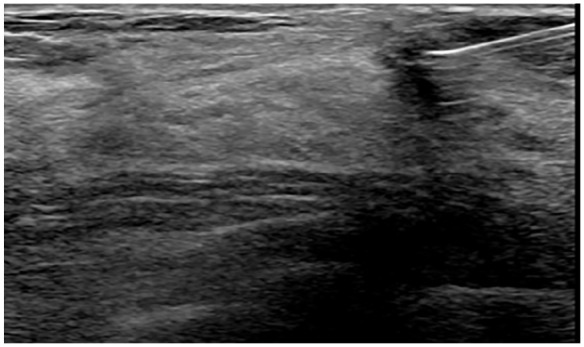

Design and methods: Forty-seven patients with non-palpable breast lesions, who underwent Magseed pre-operative localization followed by breast-conserving surgery between November 2022 and June 2024 at our Breast Unit were enrolled in our study. The procedure involved percutaneous placement of the Magseed into the target lesion under ultrasound (66%) or stereotactic (34%) guidance. Data on patient demographics, lesion characteristics, Magseed localization and retrieval, surgical outcomes, and complications were collected and analyzed.

Abstract Image